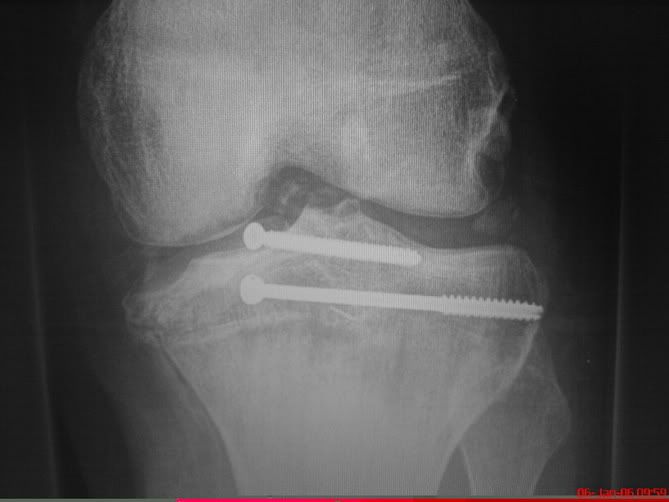

å så var jeg inne til undersøkelse igjen (fortsatt poli-klinikk..) Å da fant legen bare ut at beinet mitt fortdsatt var ødelagt... Men nå skulle han snakke med resten av overlegene (tror det er 20 overleger på Ortopedisk på Ulevål....)... Dette resulterte i at jeg blei kalla inn til undersøkelse igjen den 14\12-2005.... Å da var det vel 7 stk "seksjons overleger" inne å så på beinet og bildene mine.... Da kom de fram til at det vil prøve og sette inn en kne-protese i beinet mitt.... (de andre mulighetene var og enten prøve og re-konstruere det som er der.... nesten umulig vistnok..... eller og amputere beinet...)

BTW: kneet er såpass ødelagt at jeg ikke kan gå på det. (alt av leddbånd og korsbåndt er "vekk") og jeg får heller ikke retta det ut... Så jeg har gått på krykker siden da...

Bilde av kneet med div skruer ol...